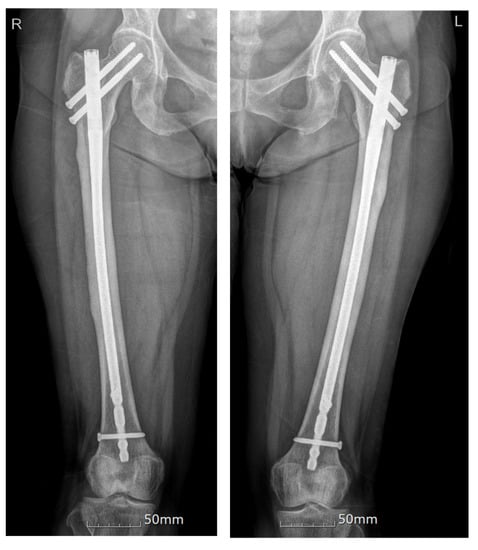

| 1 | Our case | F, 64 | O/O | Simultaneous | Ibandronate 150 mg monthly for 10 years | Prox/prox | PIM nailing/PIM nailing | Teriparatide | NA |

| 2 | Ken Iwata et al., 2017 [10] | F, 68 | X/X | Sequential (1.5 years) | Alendronate 35 mg, weekly for 20 months | Prox/prox | IM nailing/PIM nailing | NA | 12 months/NA |

| 5 | Eric D. Van Baarsel et al., 2019 [1] | F, 63 | O/O | Simultaneous | Alendronate for unknown period | Prox/prox | PIM nailing/PIM nailing | NA | NA |

| 22 | Yil Ryun Jo et al., 2013 [8] | F, 75 | O/O | Simultaneous | Alendronate 70 mg weekly for 8 years | Mid/mid | Plate-screw fixation /PIM nailing | None | NA |

| 23 | Kosuke Hamahashi et al., 2020 [29] | F, 57 | O/O | Simultaneous | Zoledronic acid for 10 years | Prox/prox | IM nailing/PIM nailing | NA | 24 months/ 15 months |

| 24 | F, 57 | X/X | Sequential (3 years) | Alendronate for more than 10 years | Prox/prox | IM nailing/IM nailing | NA | 25 months/ 58 months | |

| 25 | F, 41 | X/X | Simultaneous | Minodronic acid for 3 years | Prox/prox | IM nailing/PIM nailing | NA | 19 months/NA | |